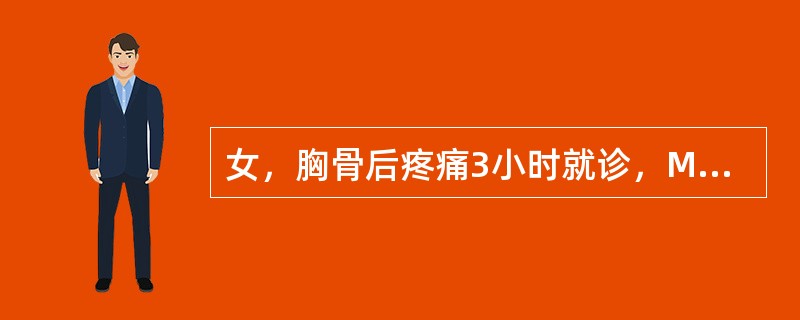

女,胸骨后疼痛3小时就诊,MRI检查如下图,应诊断为

A.主动脉瘤

B.主动脉夹层(DeBakeyⅠ型)

C.主动脉夹层(DeBakeyⅡ型)

D.主动脉夹层(DeBakeyⅢ型)

E.主动脉血栓

女,胸骨后疼痛3小时就诊,MRI检查如下图,应诊断为( )。<br /><img border="0" style="width: 389px; hei

[单选题]女,胸骨后疼痛3小时就诊,MRI检查如下图,应诊断为( )。A.主动脉瘤B.主动脉夹层(DEBAKEYⅠ型)C.主动脉夹层(DEBAKEYⅡ型)D.主